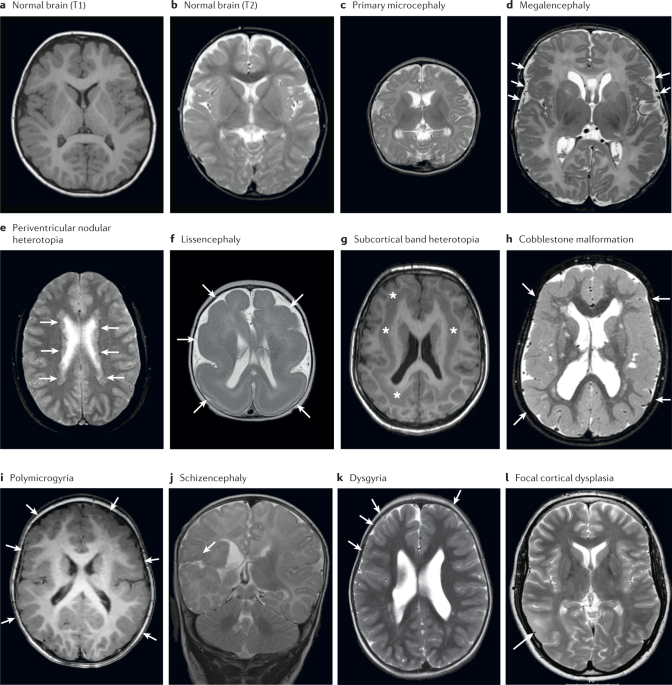

Developmental malformations that are due migration issues? organizational? Proliferation?

Migration: lissencephaly (type 2=cobblestone), heterotopia

organization: schizencephaly and polymicrogyri

proliferation - microcephaly, hemimegalacephaly